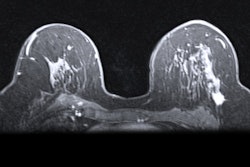

Contrast-enhanced mammography (CEM) may be an efficient diagnostic workup method for women undergoing breast cancer screening who have been recalled, suggest findings published on 3 July in the Lancet Regional Health Europe.

Researchers led by Dr. Marc Lobbes, PhD, from Maastricht University Medical Center in the Netherlands, found that CEM achieved a diagnostic accuracy comparable to that of conventional breast imaging. However, the results favor CEM’s use due to better efficiency in terms of resources used, as well as more occult lesions being detected.

The Lobbes team presented findings from the RACER trial, a multicenter, randomized controlled clinical trial that compared CEM to conventional imaging (such as digital mammography or DBT) as a primary breast imaging modality in a real-world scenario. It also evaluated diagnostic workups in women recalled from breast cancer screening. Lobbes said that to the best knowledge of the researchers, this trial is the first of its kind.